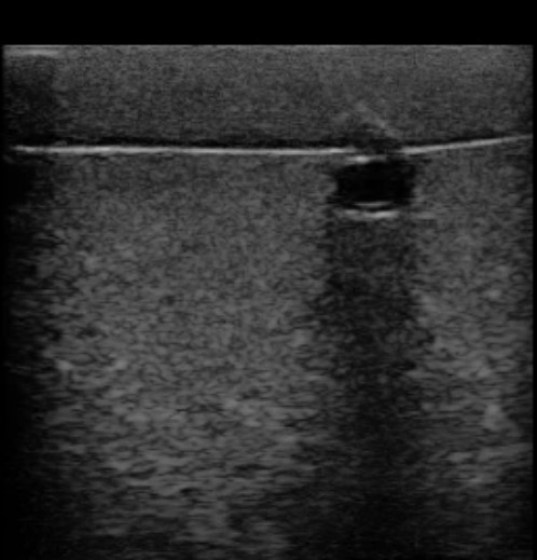

Systém Simulab Ultrasound Guided IV Access Arm System je anatomicky přesný model pro zajištění žilního vstupu zavedením katétru do periferní žíly. Model pravé paže je kompatibilní s jakýmkoliv ultrazvukovým přístrojem a obsahuje hmatovou a ultrazvukovou anatomii.

Společnost Simulab vnesla do tohoto nového simulátoru svou vynikající technologii měkkých a ultrazvukem měřitelných tkání. Byl zkonstruován tak, aby poskytoval realistický tréninkový zážitek v odolném a snadno použitelném systému, který usnadňuje výměnu cév.

- Identifikace pažní tepny, bazilikální, hlavové a střední kubitální žíly pod ultrazvukem.